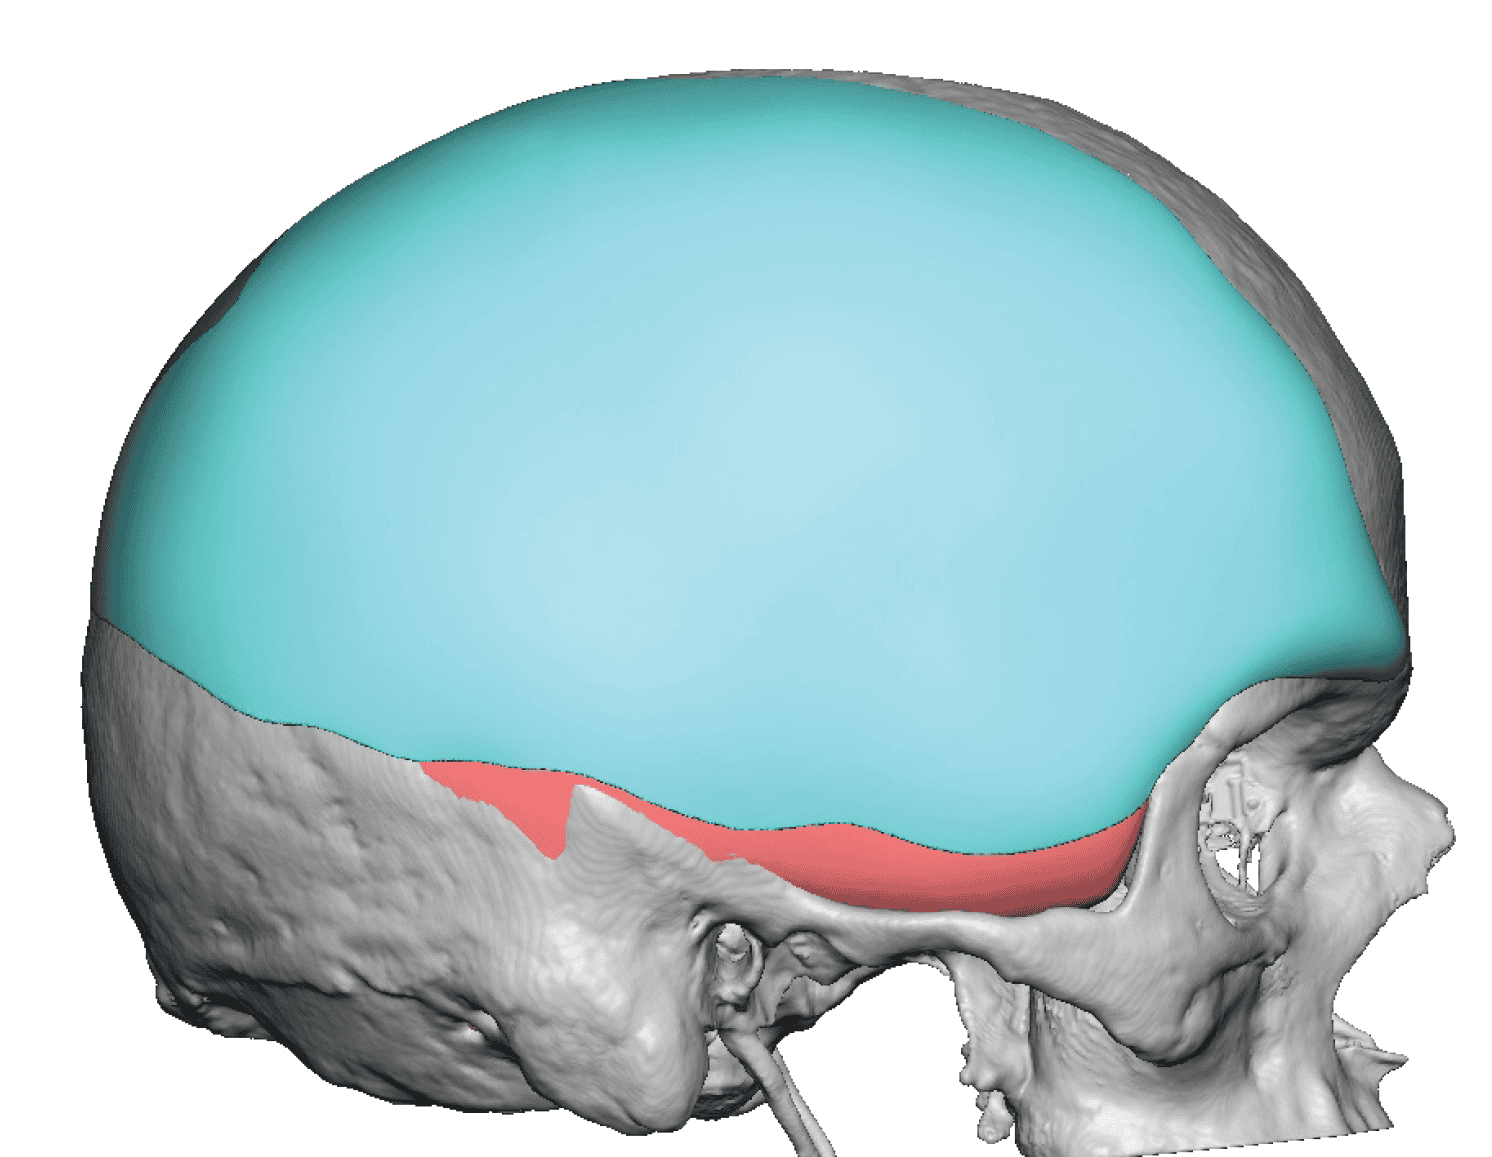

Severe narrowing skull deformity from prior sagittal craniosynostosis repair as an adult.

Complete replacement of entire skull by a custom implant with temporal fat injections.

Severe narrowing skull deformity from prior sagittal craniosynostosis repair as an adult.

Complete replacement of entire skull by a custom implant with temporal fat injections.